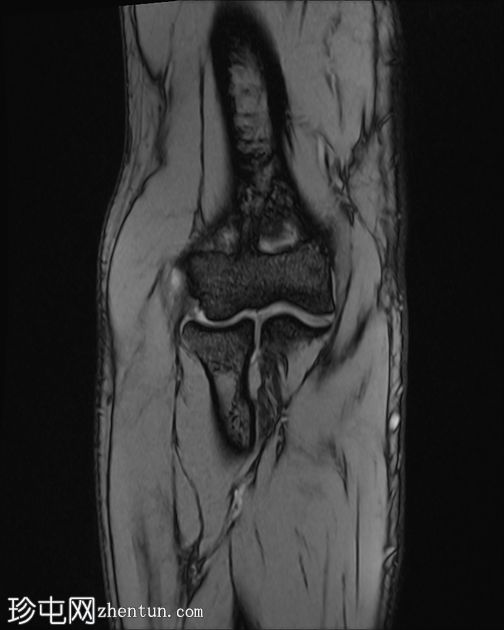

冠状位

梯度回波序列

肘关节伸肌总腱增厚,腱内可见高信号及部分撕裂。伴周围软组织水肿。

本病例展现了网球肘的典型

影像

学特征。